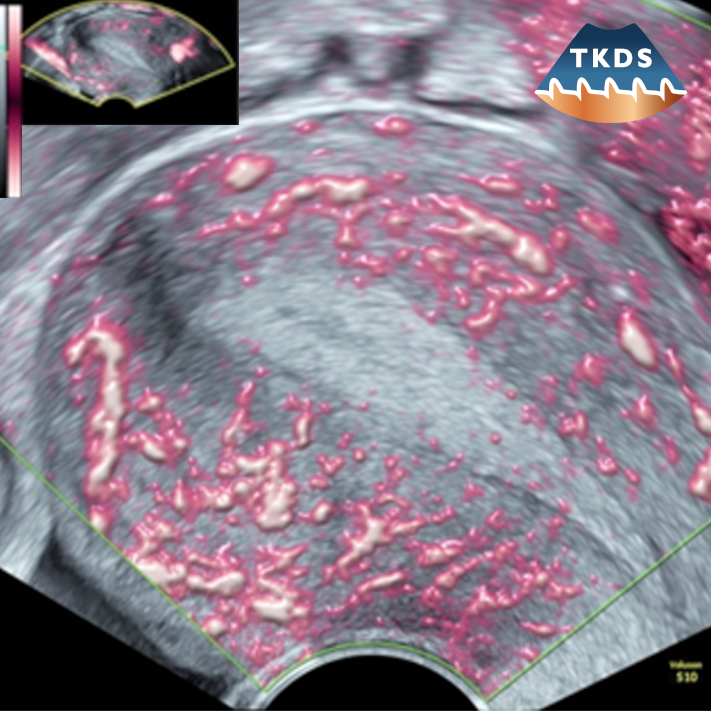

Die Dopplersonografie ist eine wertvolle additive Methode in der geburtshilflichen Ultraschalluntersuchung, der Sonografie des weiblichen Beckens und der Mammasonografie.

Als hochspezielisierte Untersuchung erfordert deren Anwendung zusätzliche Qualifikationen, verantwortungsvollen Einsatz ssowie kritischen Umgang mit den Ergebnissen und den aus diesen sich ergebenden Konsequenzen.